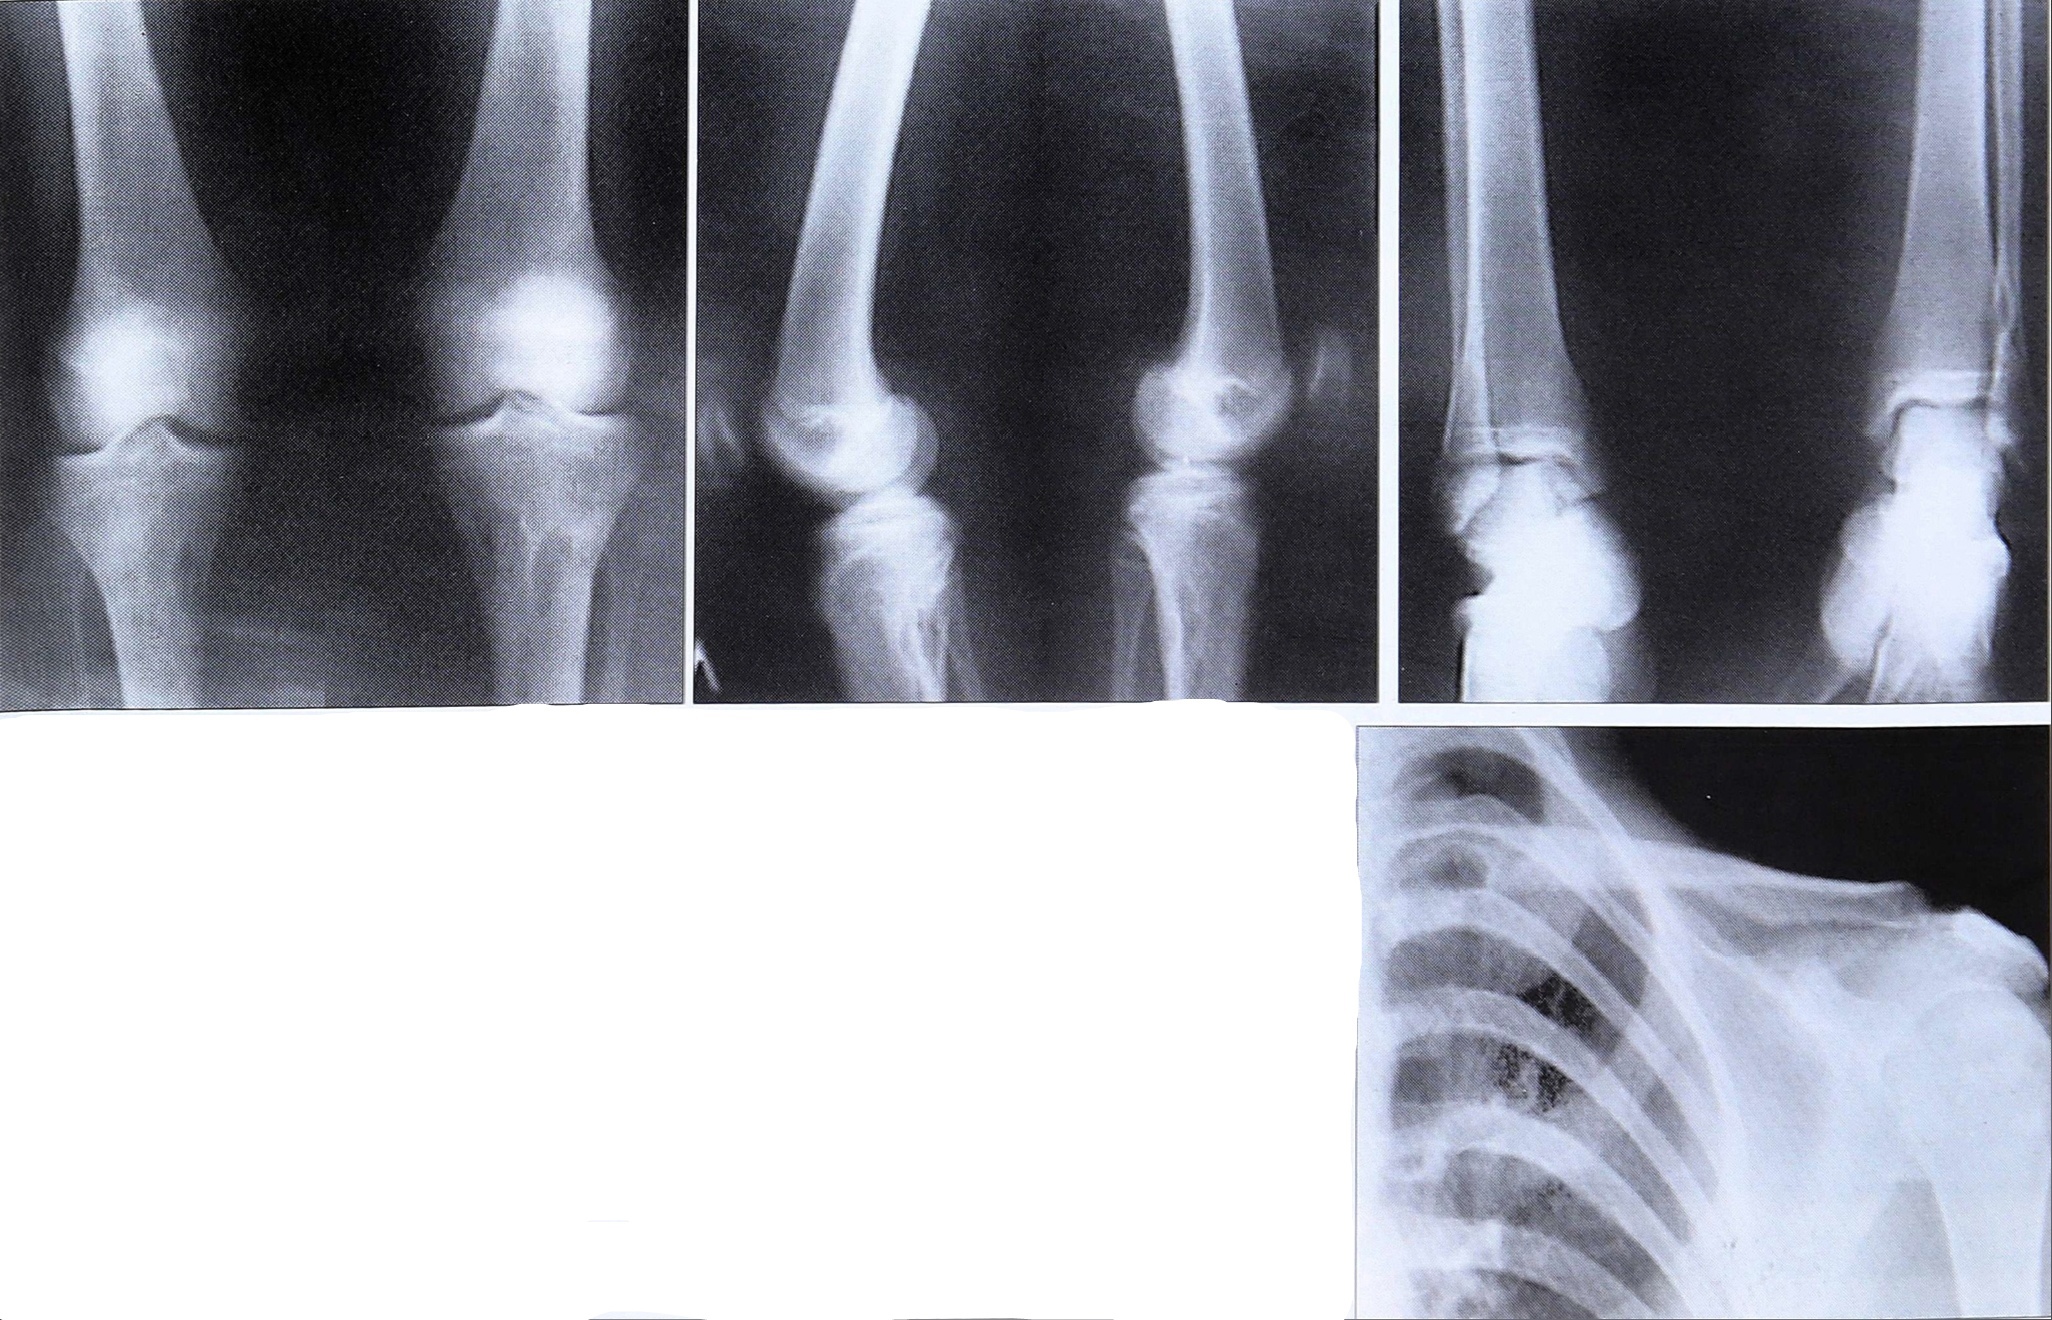

В связи со скудностью клинической картины МФДК наибольшее значение в диагностике имело рентгенологическое исследование скелета. Рентгенологическая картина при полиоссальной форме МФДК характеризовалась наличием множественных эксцентрично расположенных краевых дефектов костной ткани в метафизарных отделах длинных костей. Дефекты никогда не были связаны с зоной роста и при динамическом наблюдении перемещались в сторону диафиза. Во всех случаях МФДК были отграничены от смежных отделов костной ткани полоской склероза. Контуры дефектов были ровные, полициклические (рис. 2).

Рис. 2. Рентгенограммы больной М. с синдромом Jaffe—Campanacci.

Учитывая локализацию и распространенность патологического процесса, мы выделяем субпериостальную и интракортикальную форму МФДК. Субпериостальная форма характеризуется поднадкостничным расположением дефекта, обычно вытянутого по длиннику кости и отграниченного от смежных отделов метафиза зоной склероза. Интракортикальная форма представлена дефектом коркового слоя и прилежащих отделов метафиза, нередко занимающим более 1/3 поперечника кости. При больших размерах дефекта мы иногда наблюдали смещение надкостницы и ее обызвествление, создающее впечатление «вздутия» коркового слоя. Периостальная реакция обнаруживалась только в случаях патологического перелома.

При ретроспективном анализе рентгенограмм больных с полиоссальной формой МФДК было выявлено, что у 9 пациентов патологические очаги имели исключительно субпериостальную локализацию, у 3 детей — только интракортикальную и у 2 больных — смешанную (сочетание субпериостальной и интракортикальной локализаций).